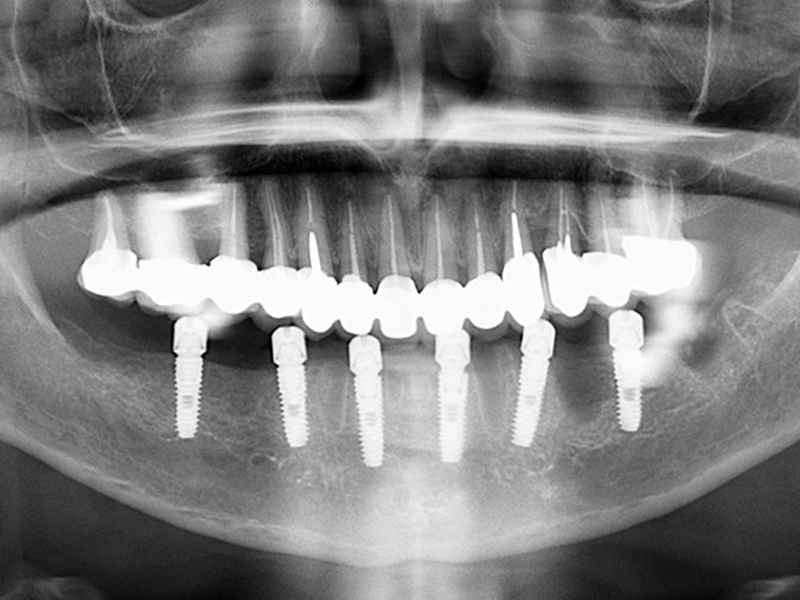

Do you want to receive the offer for your treatment?

Send us the dental x-ray and leave us your contacts, you will get a free quote in the shortest time possible. Here you can load the x-ray

Alternatively you can directly call us on our green number +441519470433 and one of our employees will answer all your questions or provide us with the contact details in the form and we will get back to you as soon as possible